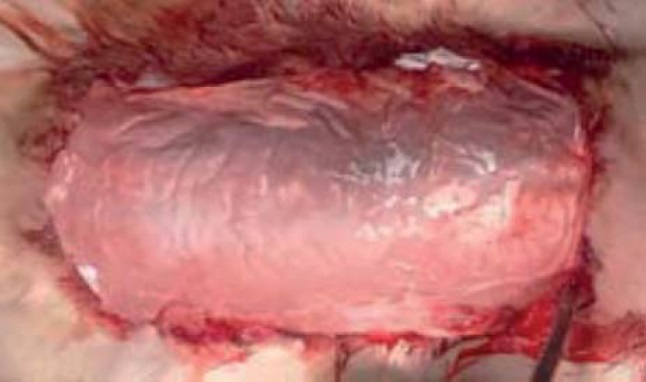

Во 2-й и 3-й группах животных спустя 60 мин после травмы под общим ингаляционным (эфирным) наркозом в асептических условиях выполняли радикальную некрэктомию до фасции и аппликацию раневых покрытий на основе природных полимеров (рис. 6).

Рис. 6. Раневая поверхность после выполнения некрэктомии